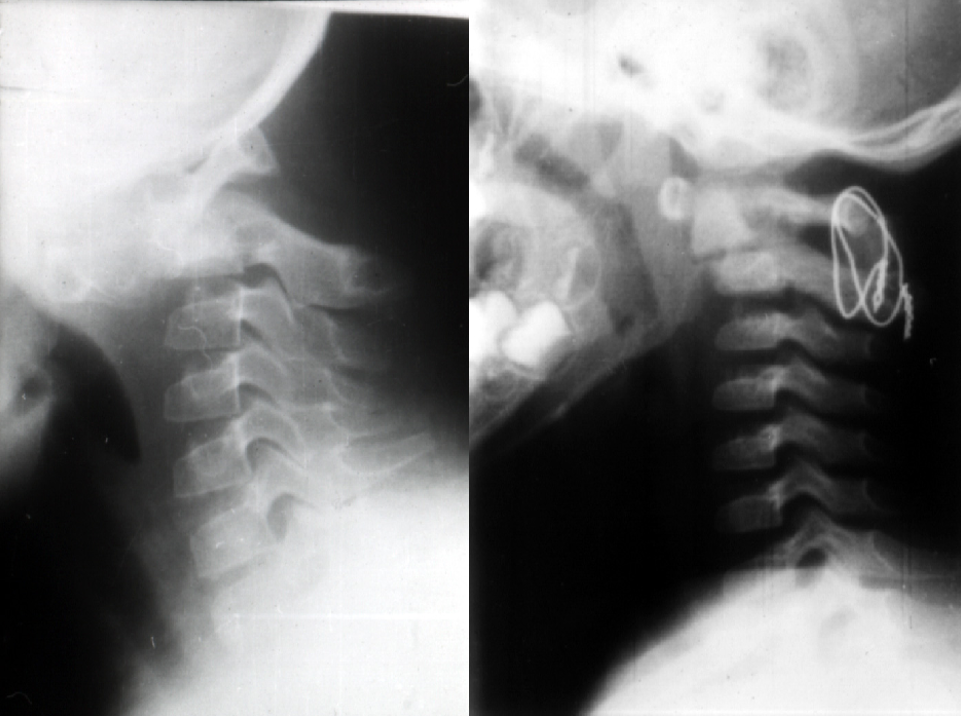

• Abumi – 矫正颈椎后凸 + 减压, 枕颈融合

病例